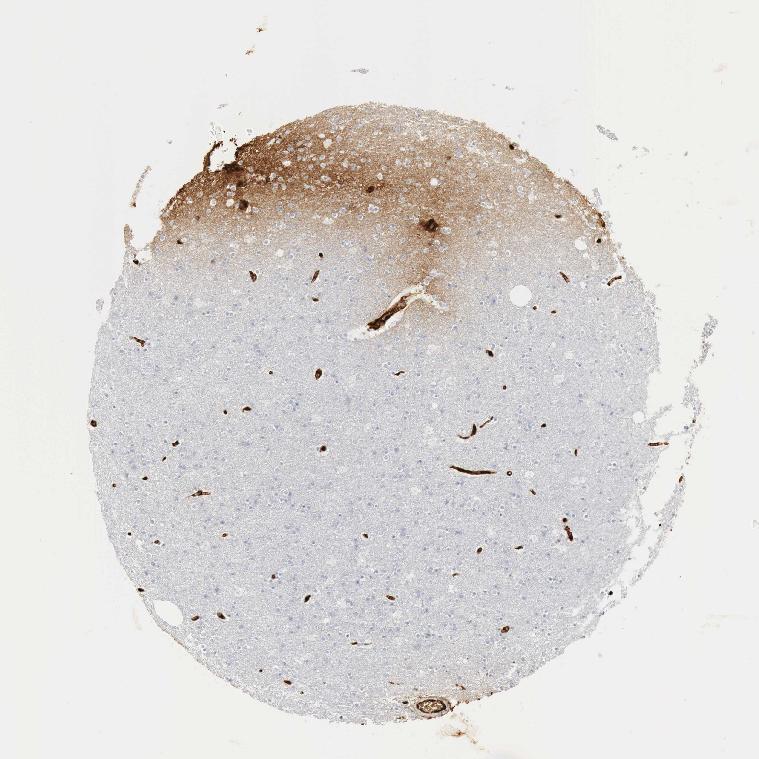

BRAIN CEREBRAL CORTEX Show tissue menu

CEREBRAL CORTEX - Expression summary

CEREBRAL CORTEX - Antibody stainingi

Antibody staining in the annotated cell types in the current human tissue is reported as not detected, low, medium, or high, based on conventional immunohistochemistry profiling in selected tissues. This score is based on the combination of the staining intensity and fraction of stained cells.

Each image is clickable and will lead to virtual microscopy that enables deeper exploration of all samples and also displays staining intensity scores, fraction scores and subcellular localization as well as patient and tissue information for each sample.

Antibody CAB000050Antibody CAB016533

Endothelial cells MediumNot detected

Glial cells Not detected-

Neuronal cells MediumNot detected

Neuropil LowNot detected